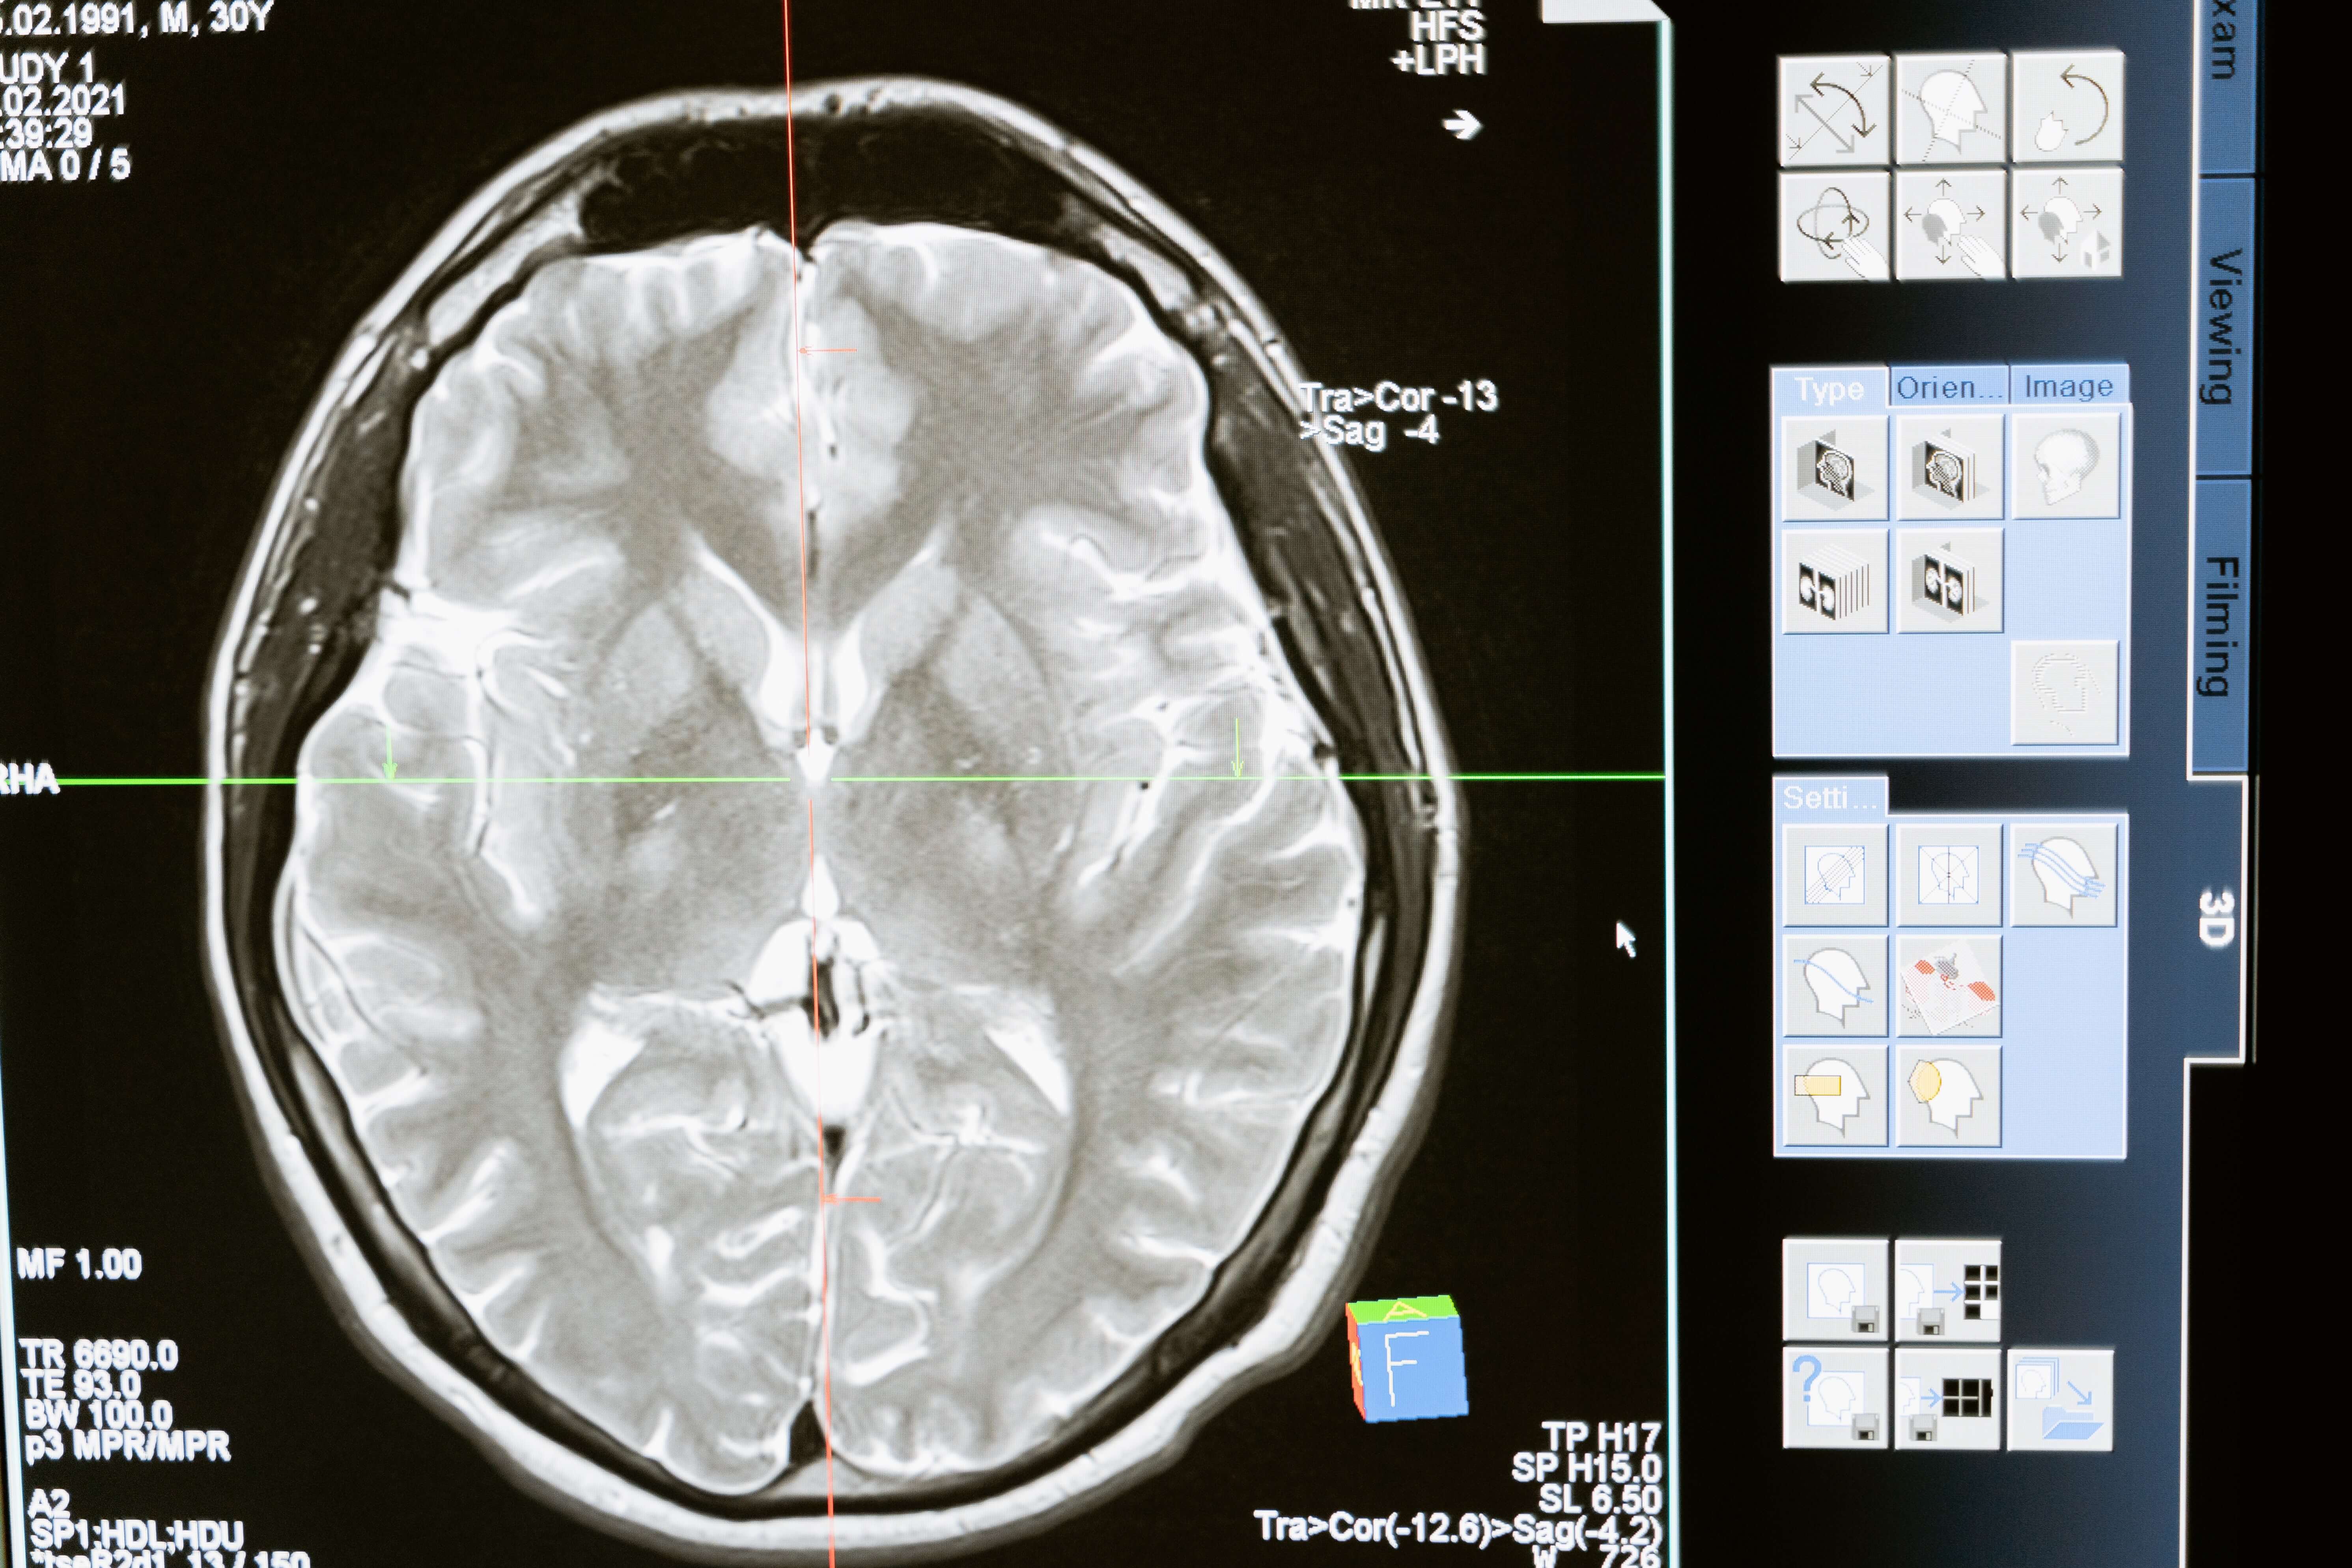

According to the Centers for Disease Control and Prevention (CDC), 1.4 million people are affected by brain injuries yearly. Out of those who suffer a traumatic brain injury, an estimated 5.3 million people require long-term care. A San Ramon brain injury attorney who has experience with these types of claims is definitely the right choice for you if you have suffered this trauma due to negligence on the part of another individual or entity.

An Injury to the Brain Can Have Serious ConsequencesIndividuals suffering from traumatic brain injury (TBI) may be affected for the rest of their lives. As a result of a brain injury, it is not uncommon for those impacted to become permanently disabled to require a long period of rehabilitation. These types of injuries can sometimes be delayed after an accident and begin with small problems such as headaches and forgetfulness to expand later into a more serious condition. Some symptoms of a TBI include slurred speech, memory problems, difficulty concentrating, seizures, and worsening headaches. The injury can even be fatal under some circumstances, especially if it isn’t treated early or complications arise.

Any accident that affects the head can result in a TBI. When negligence by another individual or entity was the reason for the injury, the injured party may wish to consult with a San Ramon brain injury lawyer to find out about recovering compensation. Accident types include:

Signs and symptoms of a TBI can depend on its severity and location. The more serious the trauma, the worse the symptoms. In addition, complications such as infection can worsen the prognosis and make recovery more difficult. Some of the symptoms of a TBI are as follows:

Photo attribution: Photo by MART PRODUCTION on Pexels.com